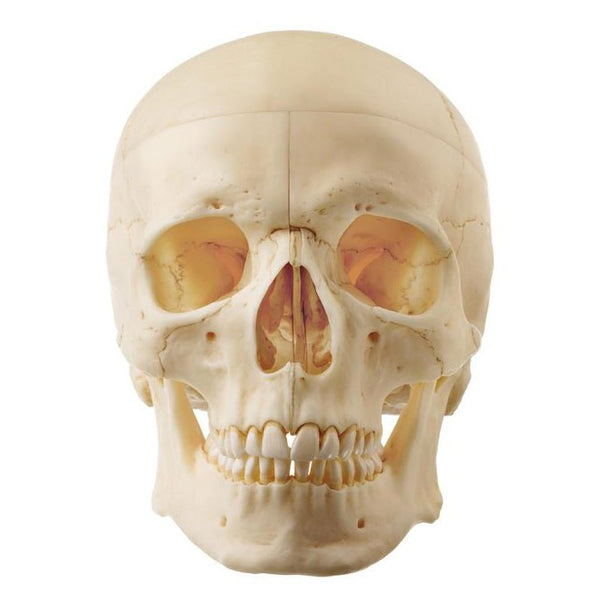

SOMSO Artificial Human Skull - 5 Parts。SOMSO 14-Pieces Model of the Skull with muscles of mastication – GTSimulators.com。SOMSO Artificial Human Skull Model, 2 parts, Removable Lower Jaw – GTSimulators.com。An109様 農薬不使用 玄米 10kg。【SOMSO】ソムソ社製品 実物大の頭蓋骨模型になります。バネのへたりなども無し。袋付きです。*解剖医学の勉強に使いました。サイズ20x13.5x15.5cm#医学部 #歯学部 #薬学部 #看護学部 #整体師 #柔道整復師 #指定校推薦 #解剖学 #予習 #解剖 #骨学 #運動器 #医療系 #医学部浪人 #浪人 #意識あげる。SOMSO Situs of the Base of the Skull。実物大の頭蓋骨模型で【頭蓋冠、頭蓋底、下顎骨の3分解】学術的に精度が高く裂、孔、突起、縫合線、歯も忠実に再現されています。頭蓋骨 模型 ソムソ社製 3分解 QS7/E。骨格模型 人体模型。緩衝材で丁寧に梱包し、付属の袋に入れた上で発送します。NISSIN シンプルマネキン simple manikin。頭部模型 somso社製 Base of the Head。*写真のように縫合部や骨の一部にシャーペンによる記入があります。【美品】等身大 人体模型 約170cm 全身骨格模型 骨格標本。入手困難・通電確認済✨デアゴスティーニ おしゃべりガイコツ ホネッキー1~70巻。*Amazon価格 ¥38,000(2024/11/12現在)*できるだけ綺麗に掃除してお送りします。天然歯牙模型 35種類 歯科技工 歯科